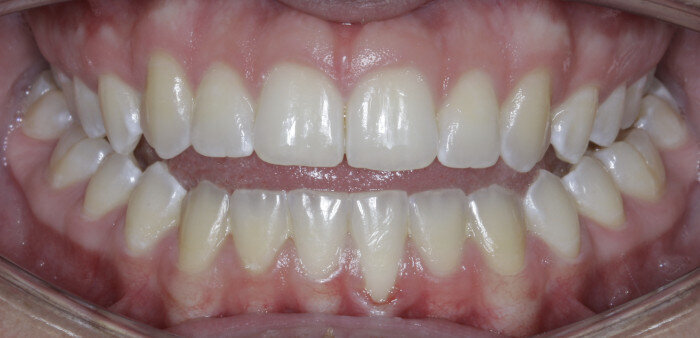

The anterior gummy smile The anterior gummy smile is one in which the patient shows excess gingival display from maxillary canine to maxillary canine (Figs. 4 & 5, beginning of treatment). This takes into account the ideal crown shape and size, where the patient has true anterior maxillary excess and is not just in need of a gingivectomy or crown lengthening procedure. To best determine if gummy smile treatment is needed in the anterior, the authentic smile photograph is used, alongside measurement of the incisor display at rest. If the resting incisor display is greater than threequarters in the adult patient without altered passive eruption, gummy smile treatment is needed. These cases are treated using two TADs placed between tooth #13 and #12 or between #22 and #23 using a 1.6 × 6.0 mm TAD. If slight posterior impaction is desired, bite turbos with Triad Gel (Dentsply Sirona) are placed on teeth #37 and #47 and squeezing exercises used to impact posterior molars engaging the posterior fibres of the temporal muscles (60 squeezes six times per day).

Fig. 4

Fig. 5

Fig. 6

Fig. 7

Fig. 8

Fig. 9

Fig. 10

Fig. 11

Fig. 12

TADs are placed at the second visit with a 14 × 25 mm copper (Cu) and nickel–titanium (NiTi) wire and are tied from the anchor to the wire with an elastic thread (surgical thread; Fig. 6). Once the patient has progressed to larger Cu–NiTi wires and stainless steel, the TADs are tied to the wire using a power chain looped to the wire, or NiTi closing springs, depending on the thickness of the tissue (Figs. 7 & 8).

Once the intrusion has been completed, the TADs are tied to the wire and vertical elastics are used to close the bite without relapse of the intrusion. If buccal crown tip is seen, owing to the movement created by the intrusion, a power chain torquing sling is used to encourage lingual crown tipping and to prevent flaring of the incisors (Fig. 9). Once the case has been completed, the appliance is removed and a gingivectomy is performed to idealise the tissue shape and the final contours are made to the hard tissue (Figs. 10–12, end of treatment).